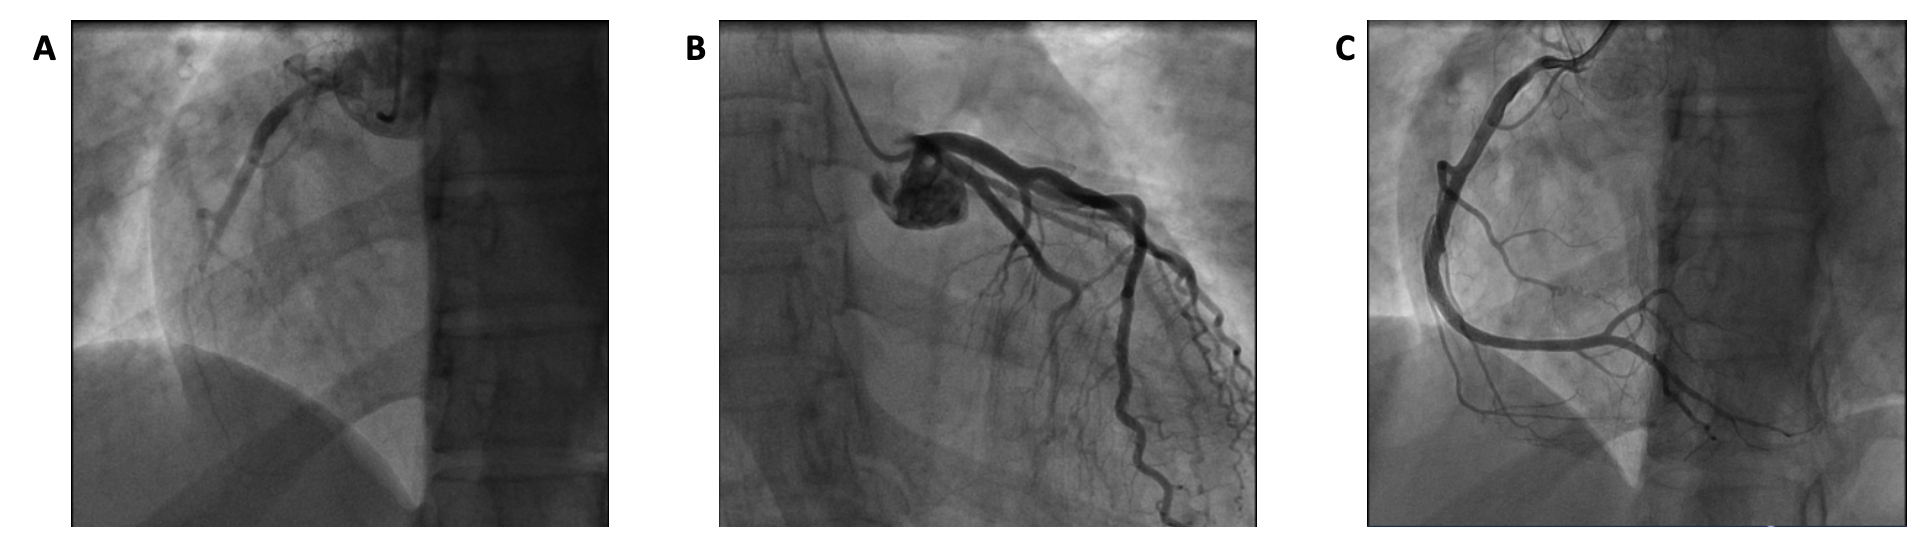

Initial vitals included blood pressure of 90/60 mmHg, and heart rate of 94 bpm. A 12-lead EKG revealed ST segment elevation in leads I, II and aVF with T wave inversions in the lateral leads (Figure 1). Initial bloodwork was notable for troponin I of 0.11ng/mL (upper limit of normal 0.034 ng/mL).